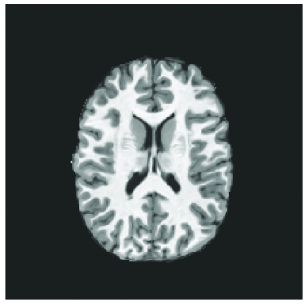

3D T1-w MRIs were pre-processed and provided by the challenge organizer. The pre-processing steps involved first creating brain masks from a series of standard brain extraction softwares including FSL BET, AFNI 3dSkullStrip, FreeSurer mri_gcut, and Robust Brain Extraction (ROBEX). The final brain mask was obtained by taking majority voting across these resulting masks. This final brain mask was used to perform bias correction and the extracted brain was segmented into brain tissue (gray matter, white matter, and cerebrospional fluid (CSF)) using Atropos. Finally the skull-stripped brain and segmented brain images were registered affinely to the SRI24 atlas [15]. Fig. 2 shows typical example of the pre-processed, skullstripped T1-w MRI and segmented brain MRI provided by the organizers.

Refer to caption

Figure 2: (a) Example of pre-processed T1-w brain MRI. (b) Example of the white matter, gray matter, and CSF segmented brain MRI of the same T1-w image.